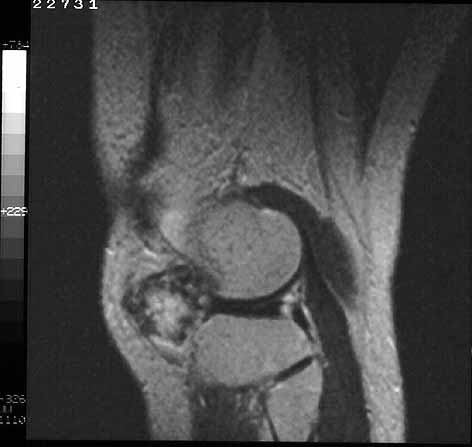

La condromatosis sinovial primaria ocasiona sintomatología monoarticular , con dolor ,inflamación y limitación funcional. Pueden afectarse las bursas y vainas tendinosas aunque la localización mas habitual es la intraarticular . La rodilla es la mas afectada, 50% de los casos, seguida de la cadera y tobillo. (28) La edad de presentación es variable y es mas frecuente en varones que en mujeres, en una proporción de 2:1. Para su diagnóstico sigue teniendo gran interés la radiología simple (29). Los signos radiográficos son muy característicos (figura 14) , si los cuerpos libres están calcificados (osteocondromatosis) , siendo difícil su interpretación si son radiotransparentes (condromatosis ). Los signos radiográficos directos consisten en la presencia de cuerpos extraños intraarticulares calcificados de tamaño variable, mas o menso numerosos pero siempre múltiples (figura 15a y b). Los signos indirectos son menso demostrativos , erosiones óseas por la hipertrofia sinovial, aumento de la interlínea articular por la interposición de cuerpos extraños o artrosis que debuta con perdidas de cartílago . La resonancia nuclear magnética permite el diagnóstico diferencial con las sinovitis y localiza la presencia de cuerpos extraños desarrollados eventualmente en las bolsas serosa contiguas. La artrografía opaca está indicada ante una sospecha clínica sin cuerpos calcificados.